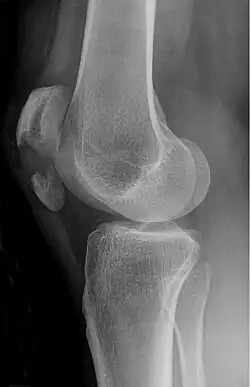

The patella can break in various ways depending on the way it is injured, and into two or more pieces.[1] Types include transverse, the most common, with one fracture line;[5] marginal; osteochondral; and the rare vertical type, or stellate, where a direct compression force gives rise to a comminuted pattern.[5][7] Patella fractures can be further classified as displaced, where the broken ends of bone do not line up correctly and separate by more than 2mm, or undisplaced and stable where pieces of bone remain in contact with each other.[1][7] If fragments of patella bone stick out from the skin it is known as an open patella fracture, and closed if the overlying skin is intact.[1]

-

Transverse fracture of patella -

Comminuted fracture of patella -

Osteochondral fracture of patella -

Vertical patella fracture